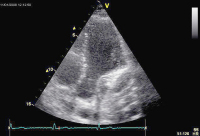

Echokardiographie aktuell: Tubuläre Struktur im Bereich des Sulcus atrioventricularis links bei 2 Patienten

Journal für Kardiologie - Austrian Journal of Cardiology 2009; 16 (1-2): 46-47 Volltext (PDF) Abbildungen mit Filmsequenzen